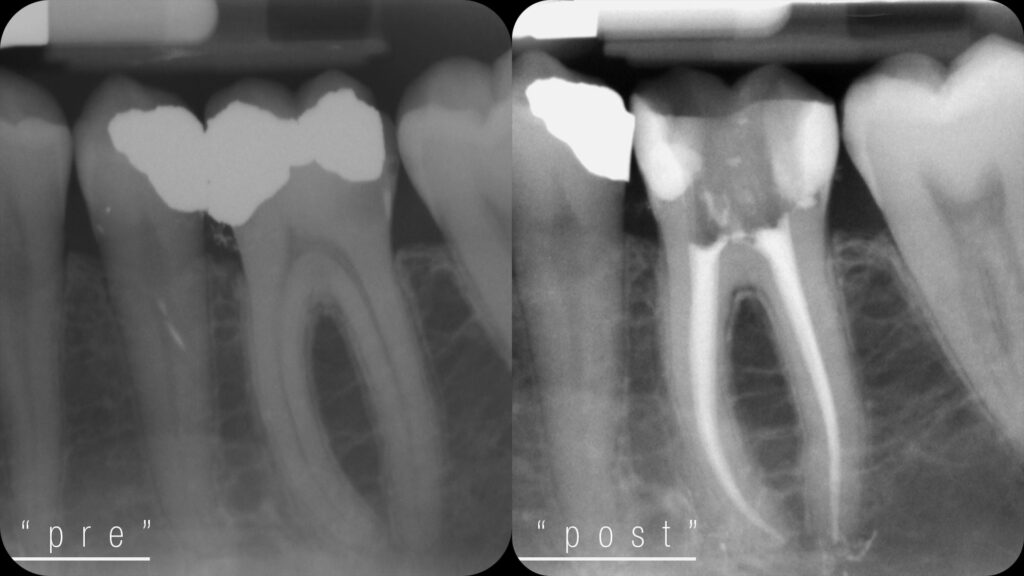

- Localizzatore apicale: ci indica con precisione fino a dove intervenire, evitando errori e trattamenti inutili.

- Motore endodontico: pulisce e sagoma i canali in modo efficace e controllato, riducendo i tempi alla poltrona.

- System B: sigilla i canali con guttaperca riscaldata, adattandosi perfettamente alla forma interna del dente.

- Siringa Obtura: consente una chiusura omogenea anche dei canali più complessi, per una terapia stabile e duratura.